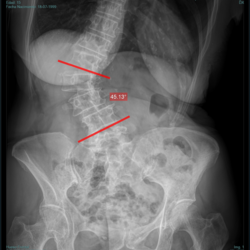

Ángulo de Cobb

Medición Férguson